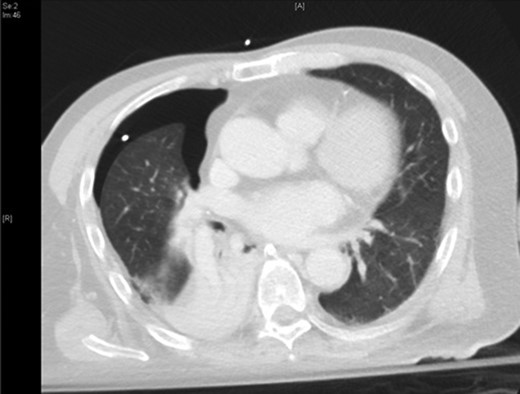

The patient was urgently reviewed by the cardiothoracic surgeons, and a small-bore chest tube was inserted, following which a computed tomography of the thorax was performed. This showed a residual but smaller pneumothorax with the chest tube in situ, associated with a small hemothorax (Fig. 3). Due to failure of conservative management and concern of a bronchopleural fistula resulting in air leak, he underwent explorative thoracoscopic surgery. Intraoperatively, an area of lung was noted with contusional changes and a bleb (Fig. 4), and a wedge resection of the right lower lobe was performed (Fig. 5). He made an uneventful recovery and was discharged.

Representative axial slice of computed tomography thorax showing a residual but smaller pneumothorax with the chest tube in situ.